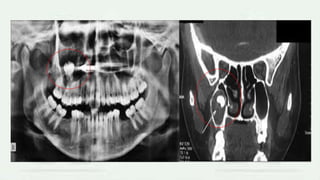

IMAGING FEATURES

 LOCATION

• the epicenter of cyst is found just above the crown of the involved

tooth,

• Important diagnostic point – cyst is attaches at the CEJ

• most commonly mandibular or maxillary 3rd molar or a maxillary

canine.

PERIPHERY AND SHAPE

• Typically have a well defined cortex with curved outline or circular

outline.

INTERNAL STRUCTURE:

• The internal aspect is completely radiolucent except for crown of the

involved tooth